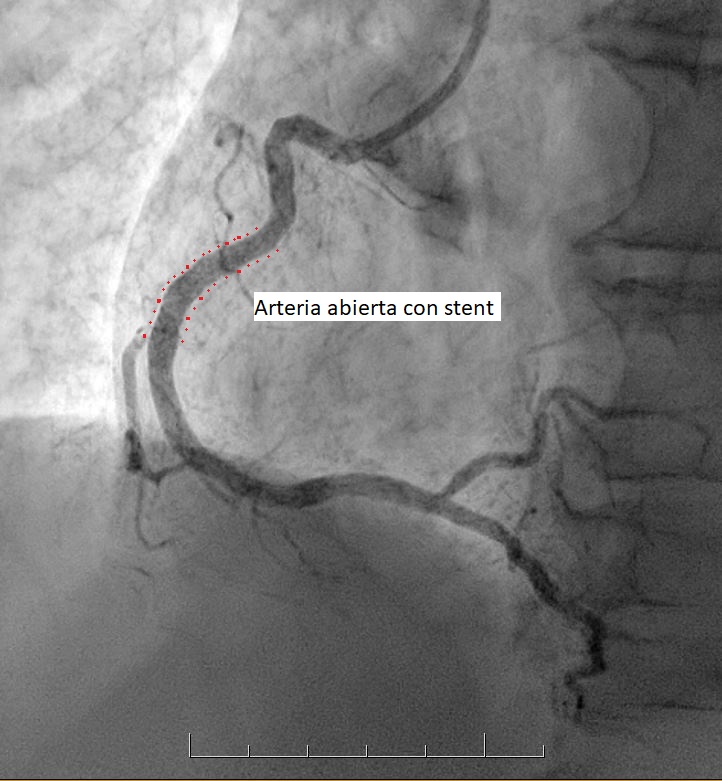

• Es un procedimiento que permite eliminar las obstrucciones de las arterias, abriendo el paso a la circulación de la sangre y dejando lugar para la colocación de un stent.

• Es un pequeño tubo de malla metálica que, una vez ubicado en la arteria, se expande y queda adherido a sus paredes, reforzando el procedimiento de desobstrucción. Se utiliza, en la mayoría de los casos, como complemento de la angioplastía y da muy buenos resultados.

Este catéter llega hasta las arterias que se van a tratar y una vez allí se inyecta una sustancia de contraste, que permite visualizar las obstrucciones existentes. A través de este catéter se inserta un balón, que se expande en el sitio obstruido y luego se retira, dejando lugar para la colocación de un stent.

Es la reobstrucción de la arteria dilatada, hecho que afortunadamente ocurre solo en un reducido grupo de pacientes. Si durante el transcurso del primer año luego de la angioplastía, la arteria tratada permanece abierta (sin obstrucciones), la evolución a largo plazo es muy buena y las posibilidades de que esta arteria vuelva a obstruirse son mínimas.